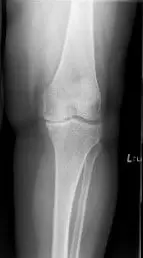

His physical examination revealed tender joint movements with crepitus. There was tenderness on the medial joint line and medial patellar facet. Imaging studies revealed bicompartmental Osteoarthritis of the knee with joint space obliteration of the medial compartment and the patellofemoral compartment.

Pre operative X-Ray of the left knee showing AP and lateral views